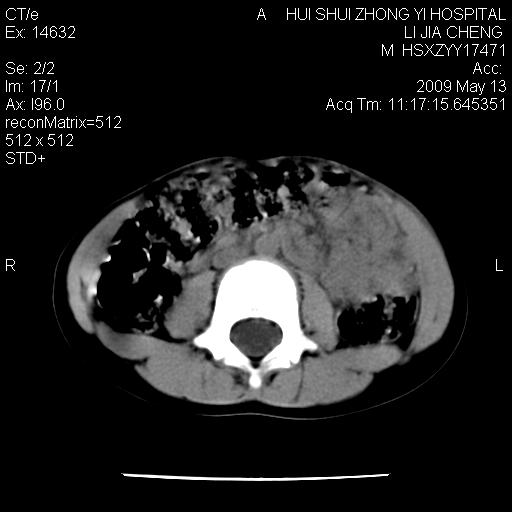

标题: PED1887:男性,6岁。反复脐周疼痛2年余。请各位老师看下腹 [打印本页]

标题: PED1887:男性,6岁。反复脐周疼痛2年余。请各位老师看下腹

该患者可自行好转,大小便未见异常,化验:便未见虫卵,血常规:wbc:8000;淋巴3600,中性45%

肠道准备不足,im15---------------------18左侧腹腔病变?

肠管管壁均匀增厚,炎性可能

是小肠,壁稍厚可能是肠腔未很好充盈所致,腹部ct扫描未见明显异常。